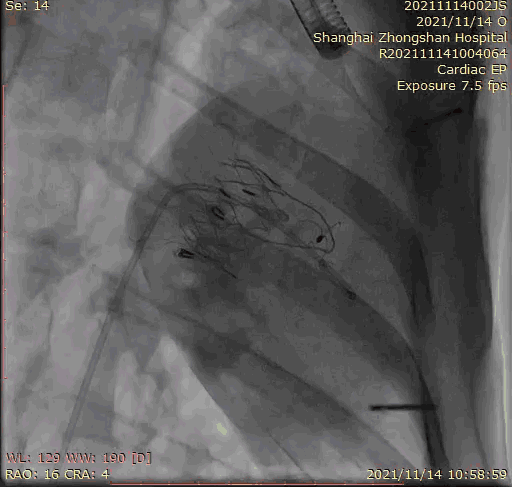

上海中山醫院葛均波院士、錢菊英院長、周達新教授、潘文志教授、潘翠珍教授、李偉教授共同完成此次臨床前研究。 術後葛均波院士對Lux-Valve Plus的器械操作效能給予了高度評價,DSA和超聲影像也顯示出在本次研究中Lux-Valve Plus的安全性和有效性俱佳。

本次臨床前研究經右側頸靜脈置入LuX-Valve Plus輸送系統可調彎鞘管,在DSA及超聲引導下將人工三尖瓣瓣膜植入到原有三尖瓣位置,利用獨特的錨定科技將人工瓣膜支架固定在預定的位置。